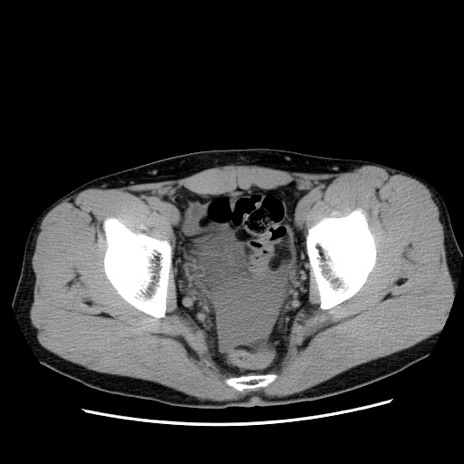

症例36(横断像)

【症例】20歳代 男性

【主訴】心窩部痛

【現病歴】今朝より上腹部痛あり。一旦軽快していたが再度出現したため救急要請。昨日夕に白身の魚を含む刺身を食べた。

【身体所見】BP 136/89mmHg、HR 74/min、BT 37.0℃、腹部:膨満、軟、心窩部に圧痛あり。反跳痛なし、筋性防御なし、腸雑音やや亢進あり。

【データ】WBC 17700、CRP 0.48